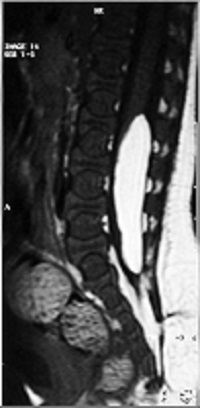

La espina bífida abierta prácticamente ya no se ve, y son el mielomeningocele, el meningocele y el mielocele. El tratamiento preventivo antes del embarazo (3 meses) y durante el embarazo (3 primeros meses) ha hecho que desaparezcan: de cualquier forma cuando ocurre, en nuestra opinión el tratamiento es la intervención quirúrgica.

La espina bífida oculta está formada por las malformaciones como los lipomas, senos dérmicos, diastematomielia, etc. que anclan la médula. Se operan con técnicas microquirúrgicas antes del año de vida.